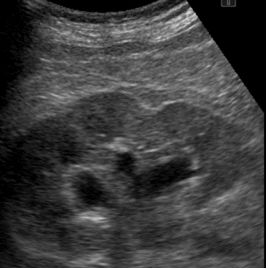

70. 35 歲男性病患因嚴重左下腹痛到急診就診,左腎超音波影像如下圖。請問何者錯誤? (A)病人有水腎(hydronephrosis)。 (B)尿液檢查可能呈現 RBC 50-100/HPF。 (C)病人乙狀結腸發炎。 (D)病人可能有輸尿管結石。 (E)飽漲的膀胱可能會造成雙側水腎。